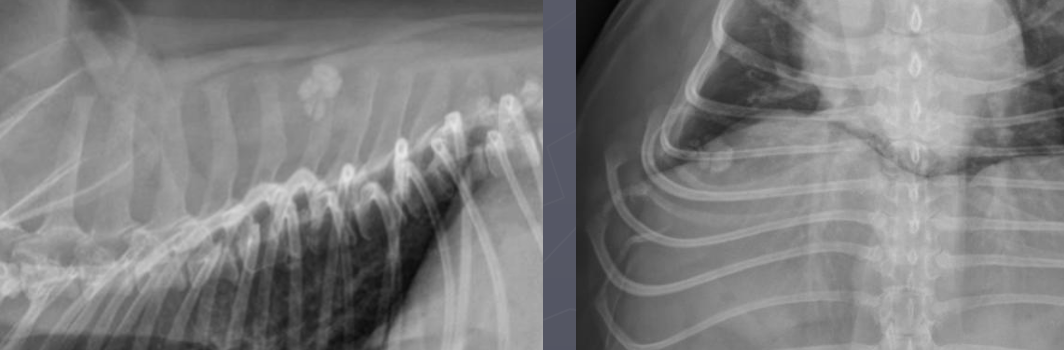

What is shown in this radiograph?

metastatic mineralization of the abdominal aorta and iliac arteries

metastatic mineralization of the iliac vessels